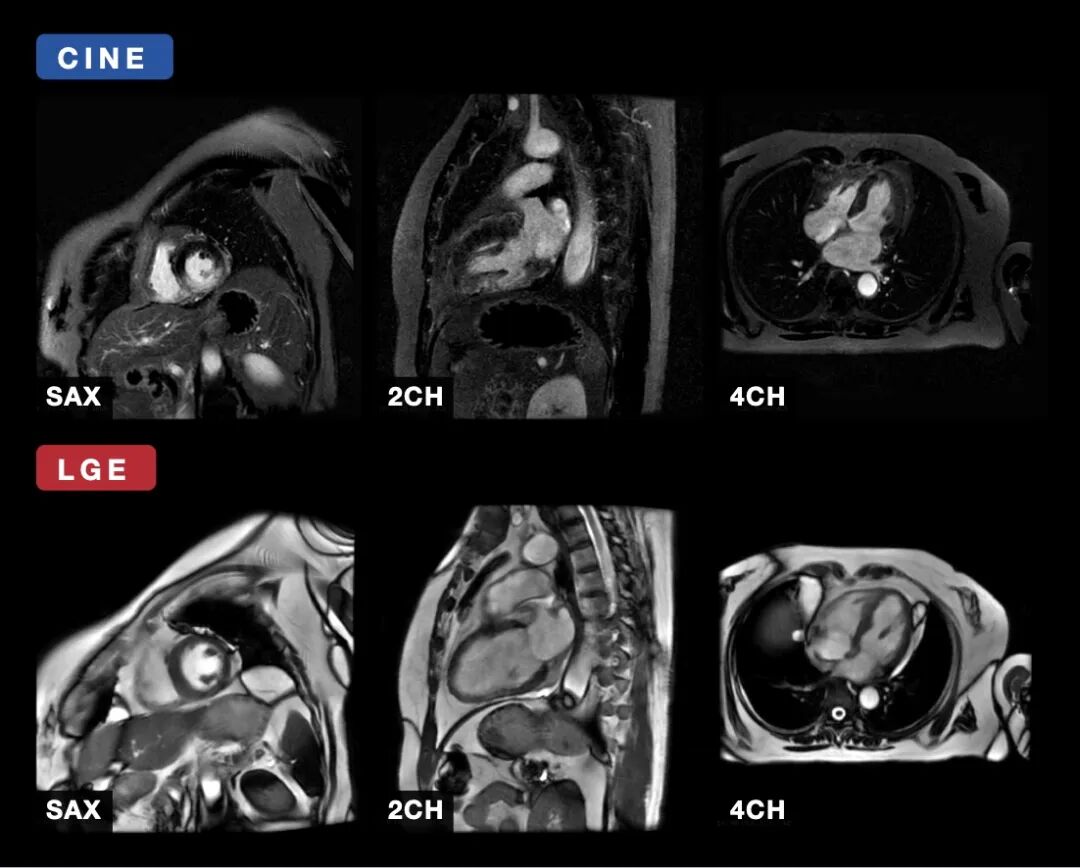

为填补这一空白,北京智源人工智能研究院、北京安贞医院、暨南大学、奥克兰大学及悉尼大学等国际顶尖学术机构联合推出 CMR-Multi Benchmark Challenge。作为大规模、多中心的心脏影像分割挑战赛,它首次统一了 4D Cine (3D+t) 与 延迟强化 (LGE) 序列,涵盖短轴 (SAX)、两腔 (2CH) 及四腔 (4CH) 全视图,并提供心室、心肌、心房及病变疤痕的专家级精准标注 。该挑战赛旨在为心脏数字孪生(Cardiac Digital Twins)和医疗大模型提供底层数据支撑,推动临床可解释、跨平台通用的 AI 技术发展 。

任务 1:Cine 多序列分割与壁运动异常分析

利用多序列 Cine 数据,实现左/右心室、心肌、左/右心房的自动分割 。

任务 2:LGE 多序列疤痕分割与定量分析

针对 LGE 序列中的心肌疤痕和房壁结构进行分割 。